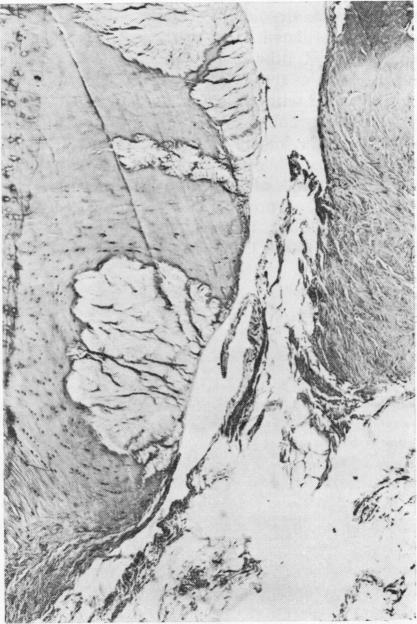

Effects of prednisolone in an experimental model of arthritis in the rabbit.

Ann Rheum Dis. 1971 Sep;30(5):509-21. doi: 10.1136/ard.30.5.509.